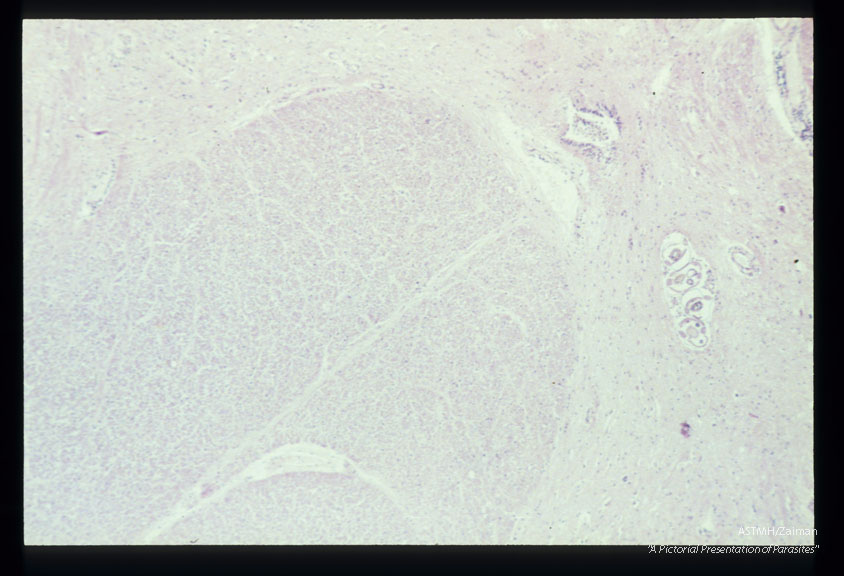

Longitudinal and cross-section of larvae in the spinal cord.

Angiostrongylus cantonensis

Description: Longitudinal and cross-section of larvae in the spinal cord.